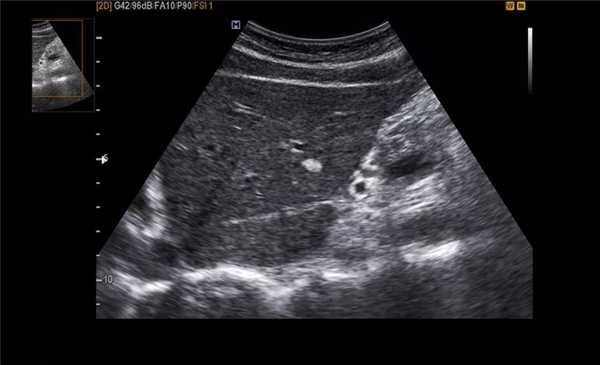

УЗИ хронических холецистит

Термин хронического холецистита используют для обозначения вялотекущего воспалительного процесса с фиброзированием стенки желчного пузыря и образованием в просвете камней.

Представлен больной с хроническими болями в правом подреберье, который ежедневно воздерживался от еды с вечера. Утолщение слабо выраженное и не является физиологическим. Также визуализируются обструкция и камень. После УЗИ данному больному был поставлен диагноз — хронический холецистит.